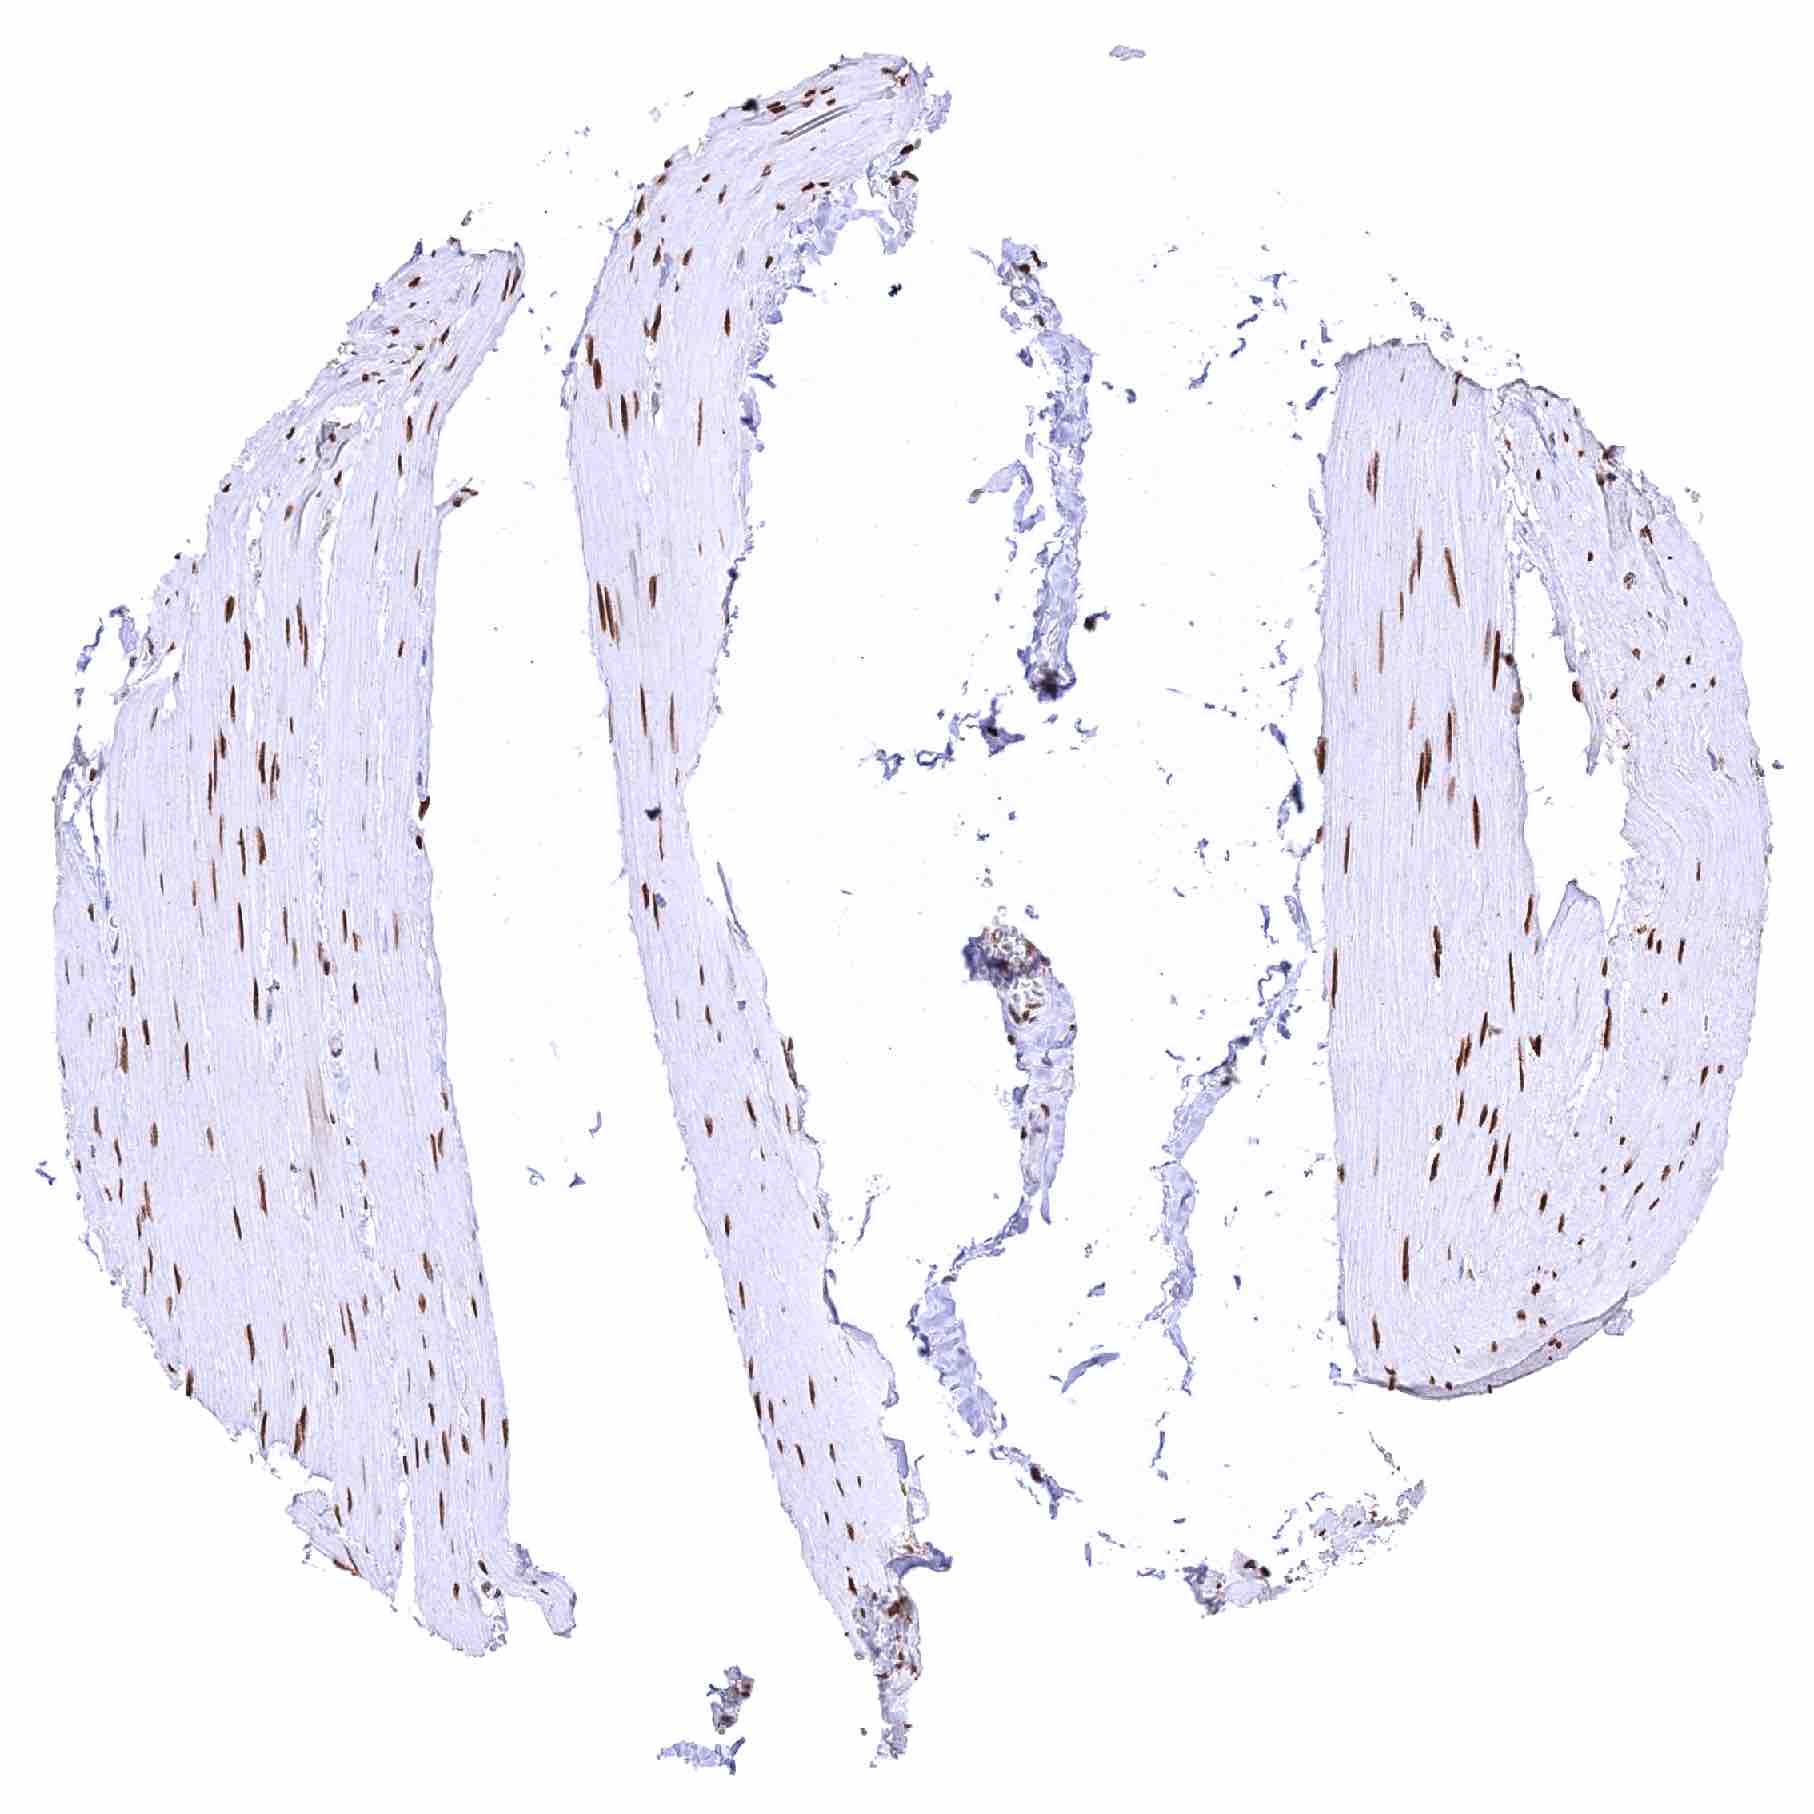

| Uterus, endocervix – Moderate nuclear NFIX staining of glandular cells. Strong nuclear NFIX staining of stromal cells |